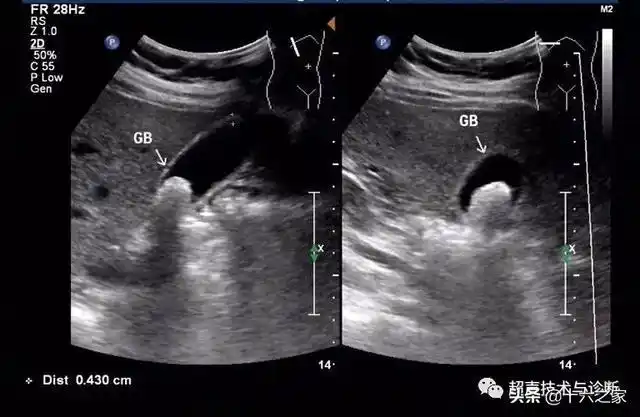

腹部超声 | 不典型胆囊结石——泥沙样结石